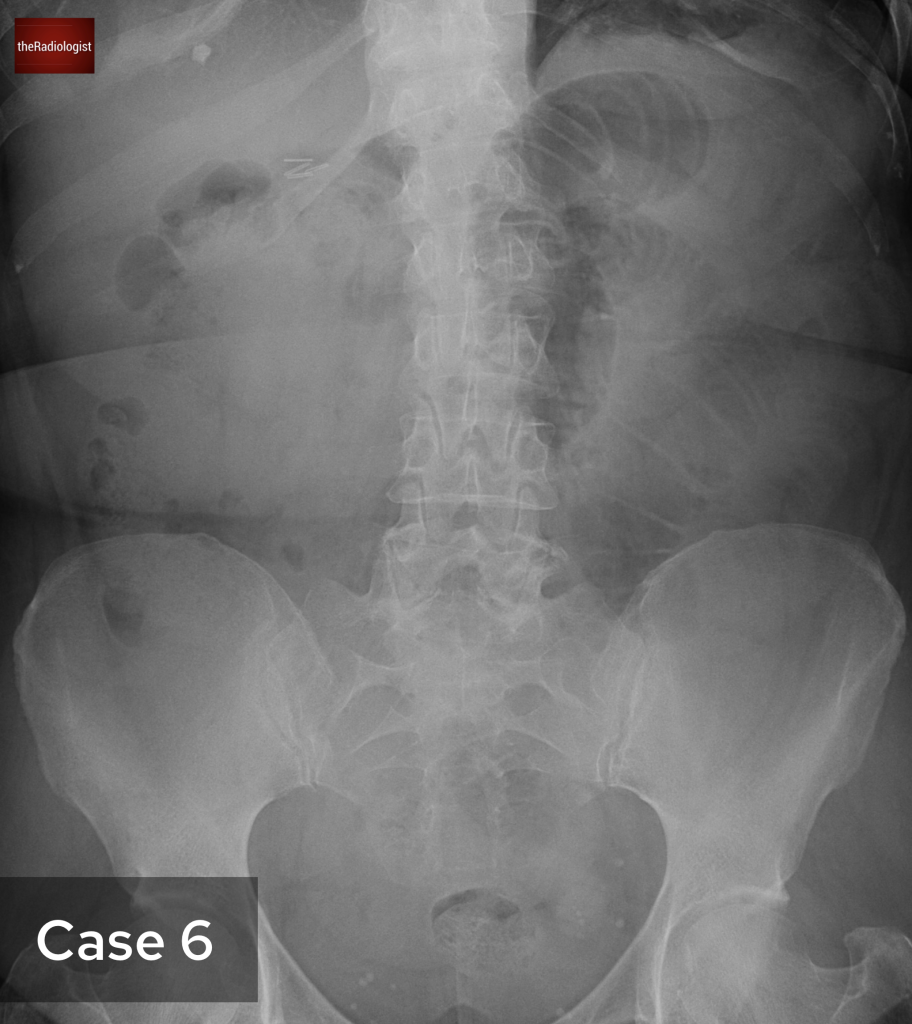

Although we couldn’t see this on our CT case, irregularity of the endplates can be seen after a few weeks on X-Ray and CT as well as loss of disc space. MRI is more sensitive and we are looking for high T2 or STIR signal within the endplates, disc and paraspinal tissues and psoas muscles. Gadolinium contrast can help as we may see enhancement of the endplates, disc and peripheral enhancement of any abscesses. It’s important on MRI to ensure there is no significant central canal stenosis secondary to abscess formation or vertebral collapse.